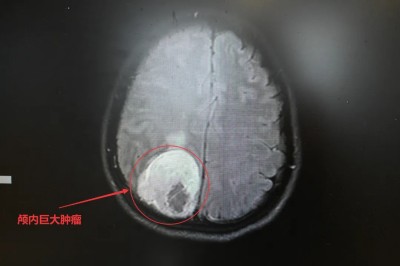

反复头晕竟查出颅内巨大肿瘤

直径达5厘米

紧紧贴附颅内核心静脉通道

3月上旬,营山黄婆婆(化名)因反复头晕在外院检查时,意外发现颅内巨大占位,手术风险极高。

随后家属陪同前往四川大学华西医院复检,再次诊断:疑右侧顶叶中央区巨大脑膜瘤,直径约5cm,肿瘤紧邻颅内核心静脉——上矢状窦,同时严重压迫右侧侧脑室。

更凶险的是,病灶位于大脑中央运动功能区,已是导致黄婆婆左侧上肢肌力下降的“元凶”。